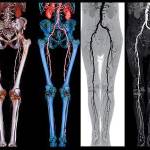

В диагностике гнойного тромбофлебита используются следующие инструментальные методы исследования:

- сонография – это метод ультразвукового исследования венозных сосудов. Он позволяет определить локализацию патологического процесса, расположение тромба, его характеристики (размеры, форму, контуры, плотность, степень прикрепления к венозной стенке). Помимо этого, оценивают состояние сосудистой стенки, клапанов и изучают параметры кровотока по пораженной вене;

- контрастная флебография – в скомпрометированную вену вводят контрастное вещество, после этого делают серию рентгенологических снимков, с их помощью оценивают ток крови, определяют локацию тромба, его характеристики, а также характеристики сосуда;

- компьютерная томография (КТ) – проводят компьютерное обследование той области, венозное обеспечение которой страдает на фоне описываемой болезни. Метод позволяет оценить вероятность возникновения тромбоэмболии;

- мультиспиральная компьютерная томография (МСКТ) – это усовершенствованная разновидность КТ, которая позволяет получить более точные результаты;

- магнитно-резонансная томография (МРТ) – ее цели и возможности те же, что и при проведении КТ, но метод более информативен при изучении мягких тканей;